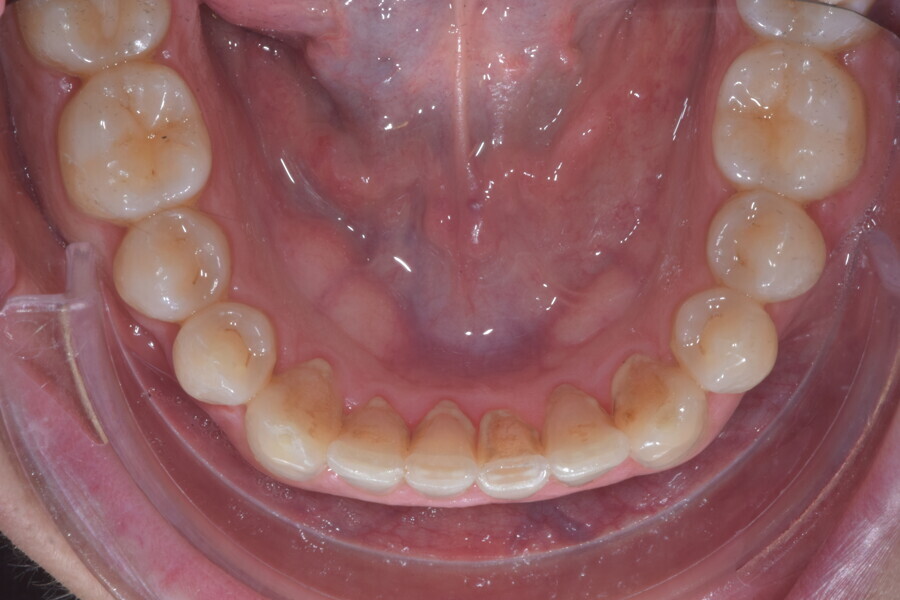

Le motif principal de consultation de ce patient âgé de 37 ans, était de rétablir l’alignement des dents antérieures sur les deux arcades. L’analyse faciale a indiqué une face courte avec un profil plat, mais une projection normale du menton (Figs. 9–12), et l’examen clinique a révélé une classe squelettique de type I (angle ANB = 0,89°) et une malocclusion de classe I avec supraclusion sévère (près de 100 %), une courbe de Spee très prononcée, un torque normal de l’incisive centrale supérieure (Ui-FH = 110°), un encombrement dentaire léger sur l’arcade maxillaire et modéré sur l’arcade mandibulaire (Figs. 13–18). Chez ce patient, les composantes de la supraclusion correspondaient à une dysmorphie squelettique grave correspondant à une hypodivergence (FMA = 14,24°), avec une inclinaison normale des incisives supérieures et inférieures et un angle goniaque réduit (110,46°). L’analyse du cliché céphalométrique indiquait une hauteur réduite de l’étage inférieur de la face associée à l’hypodivergence (Fig. 19). La seule option de traitement envisagée était un traitement orthodontique par aligneurs avec tous les éléments auxiliaires décrits (rampes d’occlusion, zones de pression, nivellement de la courbe de Spee dans les trois dimensions, élastiques de classe II et puissants contacts occlusaux) afin de corriger la supraclusion.

Le plan de traitement numérique (ClinCheck) avait prévu douze aligneurs pour l’arcade maxillaire et dix-sept pour l’arcade mandibulaire. Les objectifs du traitement visaient à combiner les mouvements verticaux d’extrusion des dents postérieures et les mouvements d’intrusion des dents antérieurs, au moyen de rampes d’occlusion, tout en utilisant des taquets d’extrusion pour assurer la désocclusion des dents postérieures et l’intrusion des dents antérieures inférieures, nécessaires au nivellement de l’arcade mandibulaire. La courbe de Spee a été nivelée et le profil plat ainsi que la position des lèvres ont été améliorés par une vestibulo-version des incisives supérieures et inférieures. Le plan avait prévu des élastiques de classe II pour faciliter la vestibulo-version des dents inférieures et les puissants contacts occlusaux postérieurs, avec une extrusion relative des dents postérieures. Une morphologie plus large de l’arcade et une intercuspidation idéale ont été obtenues par des mouvements de torque proches de 0° des dents latérales et postérieures supérieures. Aucune conception technique excessive n’avait été prévue dans le plan de traitement numérique. En raison de l’âge du patient, les aligneurs ont été changés tous les dix jours, dans le cadre d’un traitement d’une durée inférieure à six mois. À la fin de la première série d’aligneurs (Figs. 20–24), un nouveau plan de traitement numérique comportant cinq autres aligneurs a été conçu, en vue d’améliorer l’intercuspidation des molaires sans élastiques. La durée totale du traitement a donc été prolongée jusqu’à 7,5 mois puisque les aligneurs supplémentaires étaient changés toutes les semaines.